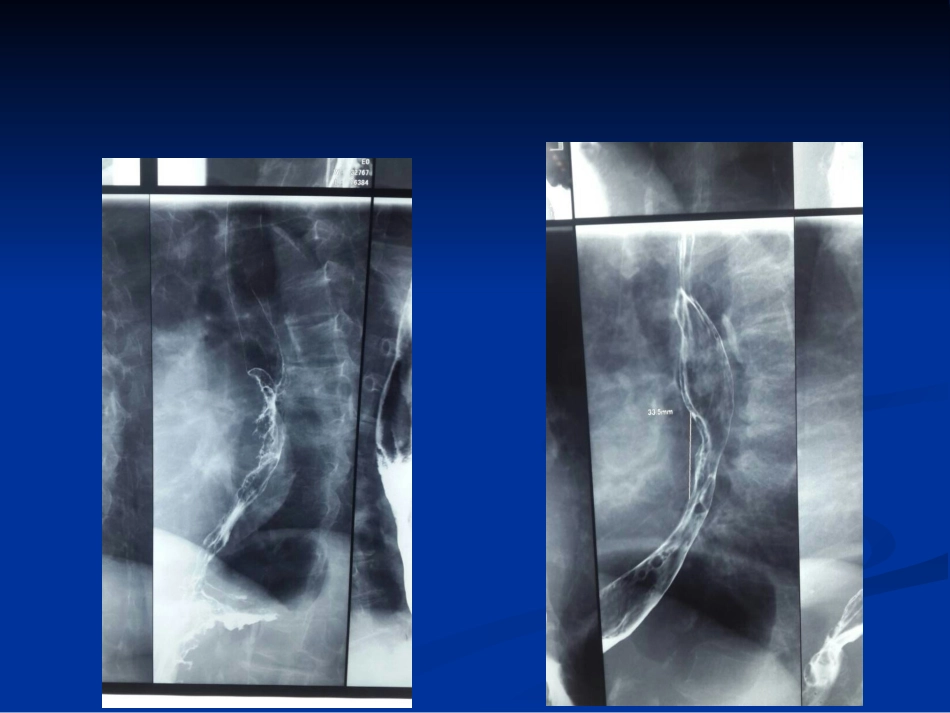

食管癌新分期食管癌新分期山西医科大学第山西医科大学第二医院二医院肿瘤放化肿瘤放化疗科晋刚疗科晋刚食管癌新分段标准食管癌新分段标准AJCC/UICC2009AJCC/UICC2009年第年第77版食管癌版食管癌TNMTNM分期标准中,重新制定了新分期标准中,重新制定了新分段标准。分段标准。原发病灶分段原发病灶分段AJCC_6thAJCC_7th解剖解剖食管镜下距离门齿距离原发病灶分段原发病灶分段AnatomicnameEsophagealLocationAnatomicboundariesTypicalesophagectomyCervicalUpperHypopharynxtosternalnotch15to<20cmThoracicUpperSternalnotchtoazygosvein20to<25cmMiddleLowerborderofazygosveintoinferiorpulmonaryvein25to<30cmLowerLowerborderofinferiorpulmonaryveintoesophagogastricjunction30to<40cmAbdominalLowerEsophagogastricjunctionto5cmbelowesophagogastricjunction40–45cmEGjunction/CardiaEsophagogastricjunctionto5cmbelowesophagogastricjunction40–45cmCT下分段奇静脉弓左下肺静脉右下肺静脉左下肺静脉右下肺静脉原发病灶分段原发病灶分段原发病灶的分段是由肿瘤上缘所在解剖部原发病灶的分段是由肿瘤上缘所在解剖部位确定位确定以前分期中原发病灶的分段是由肿瘤中心以前分期中原发病灶的分段是由肿瘤中心位置决定位置决定分段根据内镜或分段根据内镜或CTCT确定确定TT分期分期————第六版第六版TT分期分期————第七版第七版TT分期分期AJCC_6thAJCC_7thTX:原发肿瘤不能确定TX:同左T0:无原发肿瘤证据T0:同左Tis:原位癌Tis:高度不典型增生T1:肿瘤侵及黏膜固有层或黏膜下层T1a:肿瘤侵及黏膜固有层T1b:肿瘤侵及黏膜下层T2:肿瘤侵及固有肌层T2:同左T3:肿瘤侵及纤维膜T3:同左T4:肿瘤侵及邻近器官T4a:肿瘤侵及胸膜、心包、膈肌T4b:肿瘤侵及气管、椎体、大血管等原位癌原位癌(carcinomainsitu(carcinomainsitu,,Tis)Tis)改为改为高度不典型增生高度不典型增生(highgradedysplasia(highgradedysplasia,,HGD)HGD),其依据是原位癌这一概念已不,其依据是原位癌这一概念已不适用于胃肠道柱状黏膜上皮肿瘤。适用于胃肠道柱状黏膜上皮肿瘤。但对于鳞状上皮覆盖的食管而言但对于鳞状上皮覆盖的食管而言HGDHGD并并不等同于不等同于TisTis,长期随访发现食管鳞状上,长期随访发现食管鳞状上皮皮HGDHGD仅仅2020%发展成为浸润癌。%发展成为浸润癌。HCD取代TisT1a:T1a:大量临床证据表明局限于黏膜层的早期大量临床证据表明局限于黏膜层的早期食管癌很少发生淋巴结转移,非常适合采食管癌很少发生淋巴结转移,非常适合采用黏膜切除用黏膜切除(endoscopicmucosa(endoscopicmucosaresectionresection,,EMR)EMR)等内镜局部治疗手段等内镜局部治疗手段..T1b:T1b:而由于食管黏膜下层富含淋巴管,肿瘤而由于食管黏膜下层富含淋巴管,肿瘤一旦侵及此处局部淋巴转移率即可达一旦侵及此处局部淋巴转移率即可达2020%%一一3030%。%。必须进行系统性的淋巴结清扫必须进行系统性的淋巴结清扫方方能达到准确分期和根治效果。能达到准确分期和根治效果。将Tl进一步细分为T1a和T1bT4T4细分为细分为T4aT4a和和T4bT4bT4a(T4a(侵犯胸膜、心包和膈肌,侵犯胸膜、心包和膈肌,可根治性切可根治性切除除))T4b(T4b(侵犯主动脉、脊柱、气管等其他邻近侵犯主动脉、脊柱、气管等其他邻近结构,结构,无法根治性切除无法根治性切除).).NN、、MM分期分期AJCC_6thAJCC_7thNX:区域淋巴结无法确定NX:同左N0:无区域淋巴结转移N0:同左N1:有区域淋巴结转移N1:区域淋巴结转移为1-2枚N2:区域淋巴结转移为3-6枚N3:区域淋巴结转移为≥7枚MX:远处转移不能确定MX:同左M0:无远处转移M0:同左M1a:锁上(上段)或腹腔(下段)M1b:其它远处转移M1:远处转移区域淋巴结定义区域淋巴结定义————第六版第六版颈段胸上段区域淋巴结定义区域淋巴结定义————第六版第六版胸中段胸下段既往淋巴结分期既往淋巴结分期RegionallymphnodesextendfromperiesophagealcervicalnodestoceliacNodes区域淋巴结定义区域淋巴结定义————第七版第七版NN分期分期————第七版第七版N1:区域淋...